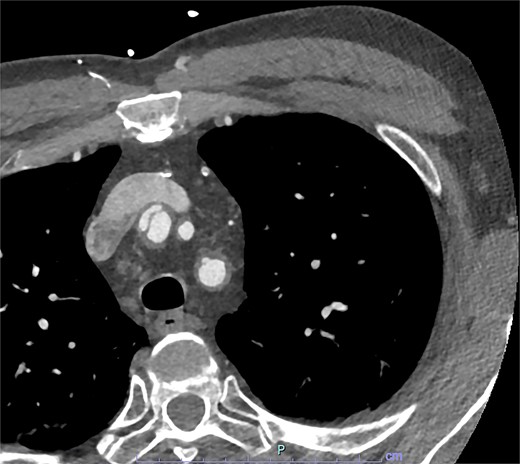

On arrive to the emergency department, the patient was found to be hypertensive with a blood pressure of 220/120 mmHg. Physical examination of the patient revealed no significant clinical findings. Serial troponins with corresponding ECG’s were undertaken which demonstrated no new evidence of myocardial ischaemia. Based upon the patient’s symptomatology, he underwent a CT aortogram which demonstrated a dissection arising from the proximal brachiocephalic artery. No dissection was noted in the ascending aorta, and there was no evidence of the brachiocephalic artery dissection extending into the subclavian or carotid arteries (Figs 1–3).

Axial slice from CT aortogram demonstrating the proximal aspect of the dissection flap.

Axial slice from CT aortogram in greater detail of the dissection flap.